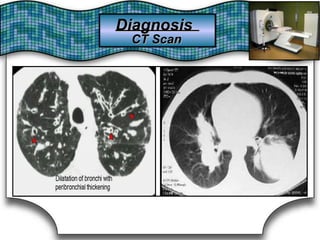

Advantages:Advantages:

1)Tomography is valuable in selected cases1)Tomography is valuable in selected cases to betterto better show theshow the

presencepresence

of lung cavities, solid masses,solid masses, and mediastinaland mediastinal & hilar& hilar LDN.LDN.of lung cavities,

2)Its2)Its complementary use with FOB givescomplementary use with FOB gives a greatera greater positive yield ofpositive yield of

pathology & is usefuluseful for excluding malignancy in high-risk patients.for excluding malignancy in high-risk patients.pathology & is

3)Allows3)Allows application of specialapplication of special imaging techniques:imaging techniques: e.g.,e.g.,

HRCT (1-3mm thickness section) →BronchiectasisHRCT (1-3mm thickness section) →Bronchiectasis

Spiral CT with pulmonary angiography →PESpiral CT with pulmonary angiography → PE